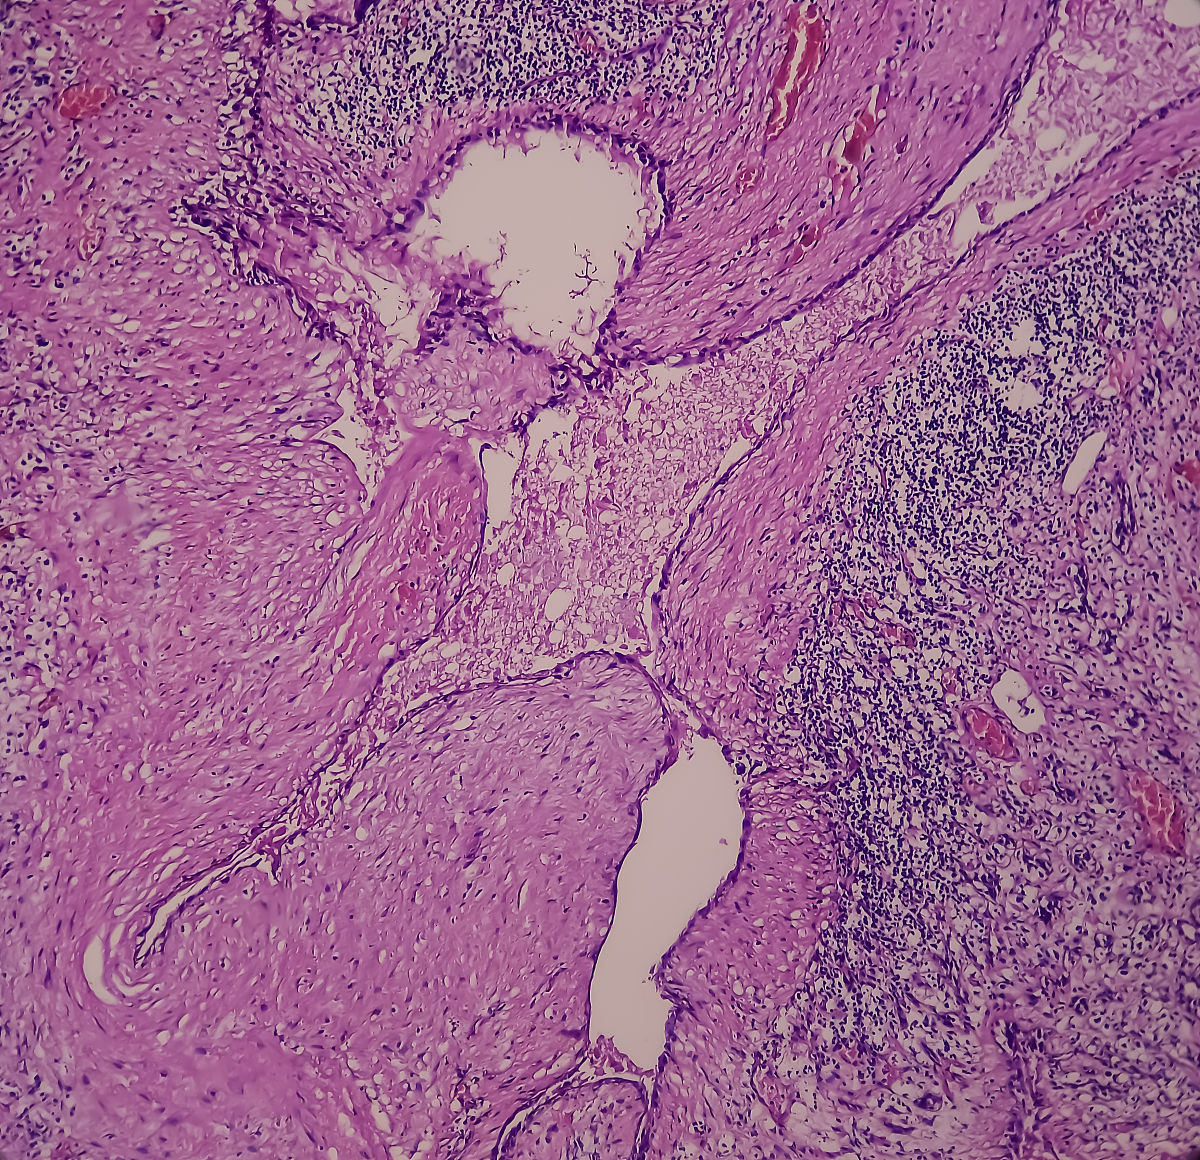

乳腺结节的手术切除是一种常见的治疗方法。对于良性的乳腺结节,手术切除可以帮助确定其性质,并排除恶性病变的可能性。对于恶性乳腺结节,手术切除是常规的治疗方式之一,通常需要结合其他治疗方法,如放疗、化疗、内分泌治疗等。

手术切除乳腺结节的具体方法根据结节的性质、大小、位置和患者的具体情况而定。常见的手术方法包括乳腺结节剜除术(乳腺结节切除)、乳腺部分切除术(乳腺保留手术)和乳腺全切除术(乳房切除术)。术前需要进行相关的检查和评估,术后一般需要进行恢复和随访。